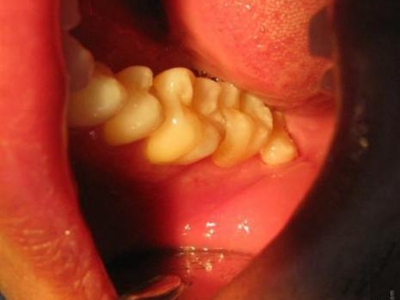

智齿冠周炎智齿周围牙龈红肿图

智齿冠周炎表现为牙列尽头智齿阻生,一部分智齿未萌出,周围的牙龈红肿,空隙变大,并有食物残渣潴留,患者自觉病变位置疼痛,并伴有张口受限及咀嚼困难。